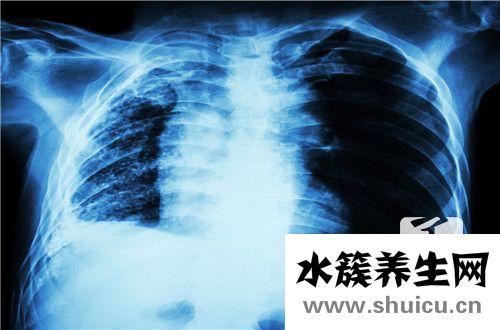

現在肺部疾病的患病率越來越高。肺炎和肺癌很常見。在某些情況下,肺部ct將顯示肺部紋理得到改善。很多人不確定是什么原因。有的是生理原因,有的是病理原因。如果沒有其他疾病,也不用太擔心。下面討...